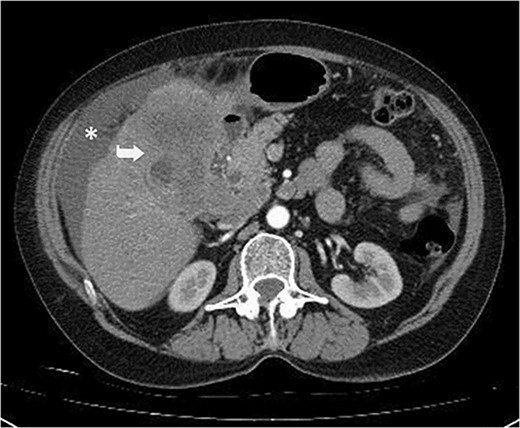

A 59-year-old woman presented with complaints of abdominal pain and abdominal distension for about a month. There was no known systemic disease and no history of previous abdominal surgery. It was learned that the patient had been admitted to the emergency department in another center one month ago with the current complaints and was discharged after medical treatment. Physical examination at the time of admission revealed abdominal distension and diffuse minimal tenderness with no signs of peritoneal irritation. Laboratory tests revealed that hemogram and biochemical parameters were within normal limits, but one of the tumor markers, the patient’s CA 19-9 level was significantly elevated at 855 U/ml (normal range: 0–37 U/ml). Contrast-enhanced CT scan showed a 10×10 cm heterogeneous mass in liver segments 4B-5, extending to segment 6, and free fluid adjacent to the liver and irregular liver contours. Borders of the gallbladder could not be seen. Soft tissues forming nodular mass formation were detected on the omental surfaces (Fig. 1). Computed tomography examination performed at the center where the patient was admitted as an emergency one month ago revealed hypodense lesions measuring 10×8 cm in size in the left lobe of the liver, protruding into the inferior perihepatic area, and 3.5 cm in diameter in segment 5 of the right lobe with no significant contrast enhancement after intravenous injection of contrast material. Perihepatic ascites was not detected and gallbladder size, wall thickness and lumen were normal (Fig. 2). In the light of the radiologic findings, a pre-diagnosis of progressive gallbladder malignancy was considered. The patient was hospitalized in the General Surgery ward for further investigation and treatment. Because of the presence of ascites causing abdominal distension, a percutaneous ascites drainage catheter was placed and 5000 cc ascites drainage was performed. Cytologic examination of the ascitic fluid revealed cell groups with unclear three-dimensional cytonuclear detail among lymphocytes and mesothelial cells with reactive atypia and malignancy was considered suspicious. With the current radiologic and cytologic findings, inoperable metastatic gallbladder carcinoma was considered. Medical treatment was decided by the multidisciplinary oncology council and 18G needle tru-cut biopsy was performed from the 10×10 cm mass adjacent to the gallbladder for definitive tissue diagnosis and adjuvant treatment planning. Histopathologic examination revealed a diagnosis of neuroendocrine carcinoma (NEC) (Fig. 3). Immunohistochemical examination revealed strong staining of tumor cells with CD56 (Fig. 4), synaptophysin (Fig. 5), chromogranin A (Fig. 6), and Ki67 index was >90% (Fig. 7). Weak staining was observed with CK19, CK7, and CDx2, but no staining was observed with CEA and CK20. Morphologic findings were compatible with small cell type. Etoposide and cisplatin chemotherapy was planned but the patient’s general condition deteriorated progressively. The patient couldn’t start chemotherapy and unfortunately resulted in mortality on the 20th day of hospitalization.

Irregular liver contours and perihepatic free fluid (*). Dense heterogeneous mass at the level of liver segment 4B-5, ~10×10 cm in area and extending to segment 6 (Arrow). Borders of the gallbladder could not be seen.